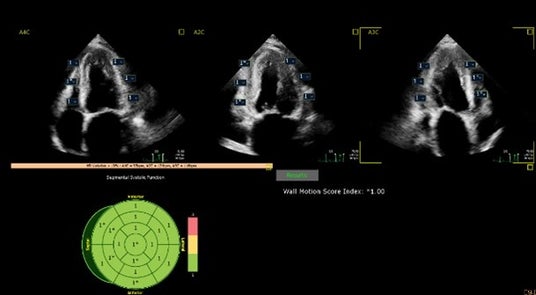

さらに、壁運動をスコアリングするAuto SWM (Segmental Wall Motion)機能は学習データを増やし、より堅牢に機能することを目指しました。